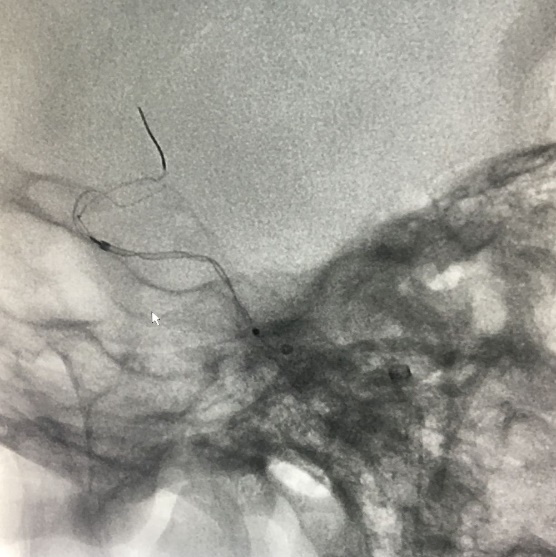

Tubridge®血管重建装置专用支架导管T-track到位,引入4.0mm*30mm支架。

准确定位后,锚定支架头端,缓慢推送支架的同时控制支架张力,顺利释放支架。

为进一步确保Tubridge®血管重建装置完美贴壁,上J型导丝支架内“按摩”。

多角度确认支架已完全贴壁。

正侧位造影示动脉瘤内造影剂明显滞留,载瘤动脉通畅,血流导向作用显著。